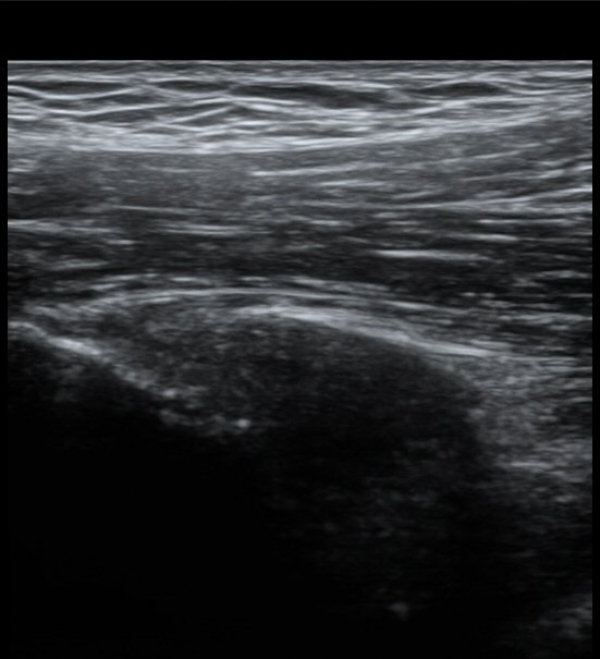

ŽÃËÀÚ¸¦ Á¶±Ý ³»ÃøÀ¸·Î À̵¿ÇÏ´Ï ÈûÁÙÀÇ °í¿¡ÄÚ°¡ ¼Ò½ÇµÇ¾î º¸ÀδÙ(»çÁø 2, 3)

ÀÌ º´Àû º¯È­´Â Á¤»óÃø(»çÁø 6, 7)°ú ºñ±³ÇÏ¸é ¶Ñ·ÈÇÏ´Ù.)